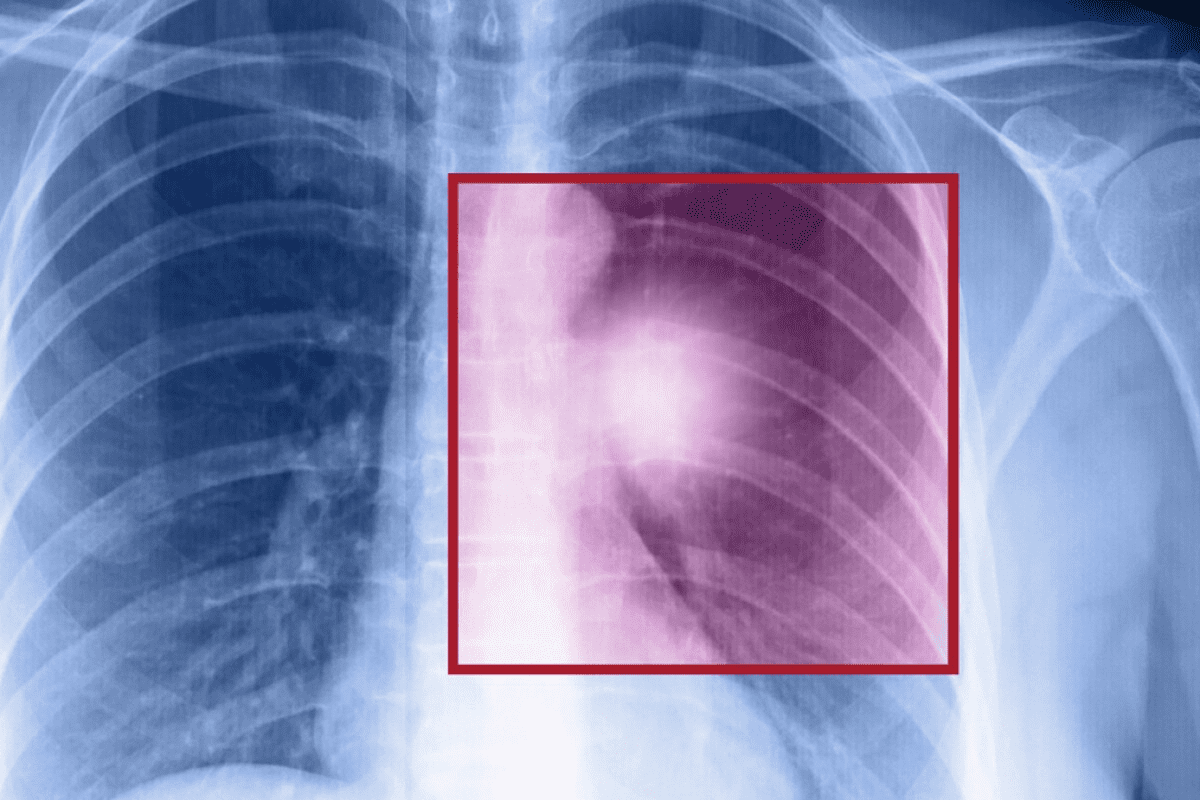

Vascular interventional radiology uses angiography and angioplasty to see and treat blood vessel diseases. These steps are key in finding and fixing problems with blood vessels.

Diagnostic and Therapeutic Applications

Angiography lets us see inside blood vessels. It spots blockages and other issues. Angioplasty uses a balloon to open up blocked or narrowed vessels, improving blood flow.

These methods are vital for treating diseases like peripheral artery disease (PAD) and coronary artery disease (CAD). They help us give full care to patients with vascular diseases.

Angiography and angioplasty start with a local anesthetic and a small cut to reach the blood vessel. A catheter is then put in and guided to the right spot with imaging like fluoroscopy.

Next, contrast dye is used to see the blood vessels through angiography. If there’s a blockage, a balloon is inflated to widen the vessel. Sometimes, a stent is placed to keep it open.